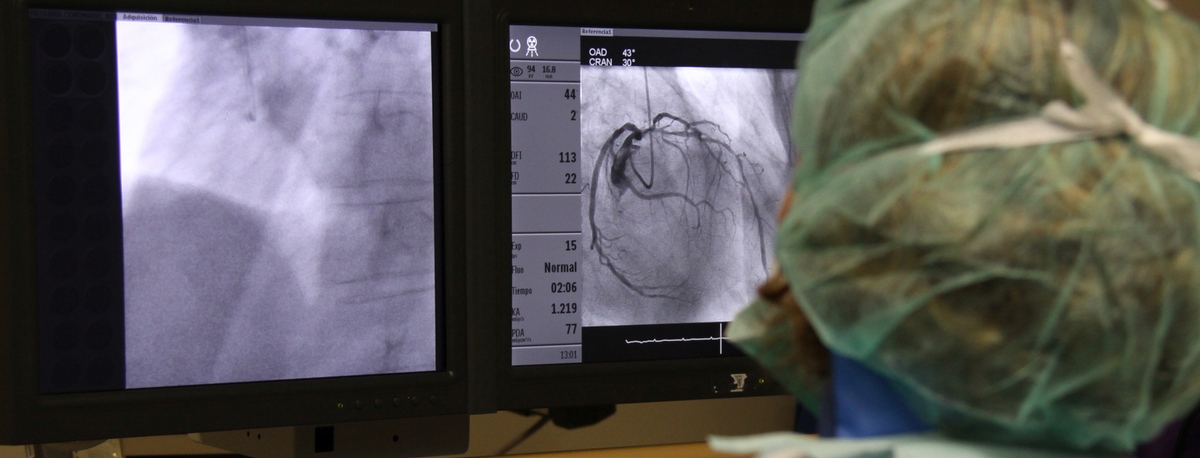

Angiología, Cirugía vascular y endovascular

Especialistas en cirugía arterial directa de extremidades, cirugía de varices, cirugía de aneurismas y cirugía carotídea

Contamos con especialistas en Angiología, Cirugía Vascular y Endovascular para el diagnóstico y seguimiento de las enfermedades del aparato circulatorio. La embolia cerebral y el tromboembolismo pulmonar son algunas de las principales causas de muerte debido a un problema vascular.

Nuestro equipo es especialista en técnicas mínimamente invasivas, utilizando técnicas endovasculares, sin cirugía, que permiten implantar prótesis vasculares para resolver dilataciones o aneurismas de las arterias. También ofrecemos todos los tratamientos de la patología venosa y arterial periférica, incluyendo las enfermedades de las arterias carótidas.